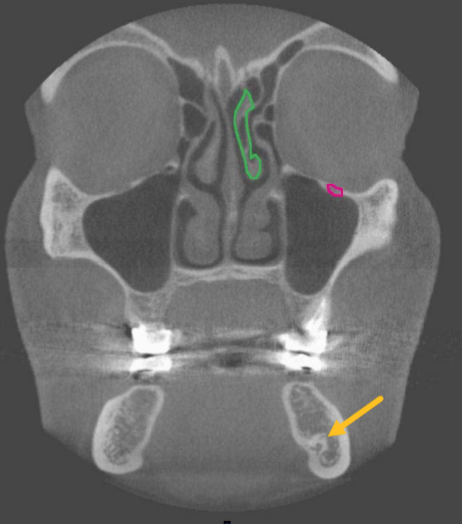

nasolacrimal duct

identify the structure

ostium (of maxillary sinus)

uncinate process

identify structure

zygomatic arch

what is indicated by the YELLOW